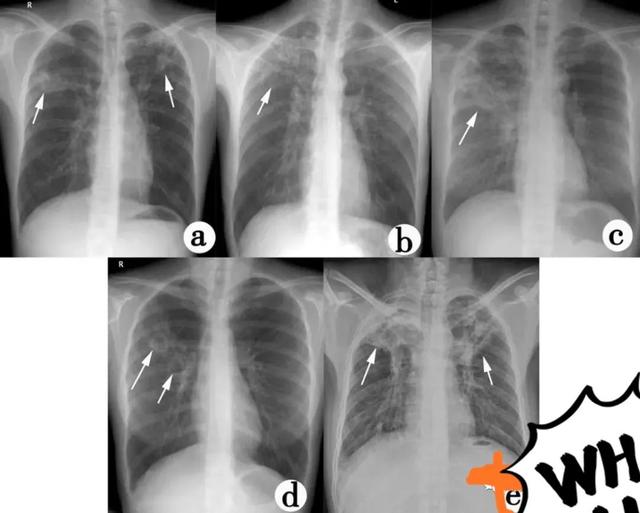

肺结核的分型诊断标准,肺结核的分型及影像学表现

a.两上肺可见斑片状影,边缘模糊;b.右上肺可见片状及结节状高密度影,右肺门上提;c.右上肺可见斑片状密度增高影,边缘模糊;d.右上肺可见片状模糊影,其内可见两个薄壁空洞;e.两上肺斑片状及条索状影,右上肺可见多发小空洞,邻近胸膜增厚,两肺门上提,两下肺纹理呈垂柳状;